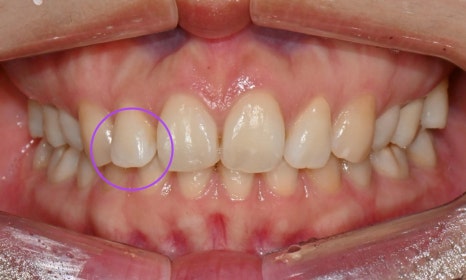

본 환자는 예전에 발치교정을 했는데 과개교합 때문에 위 치아 유지장치 관리가 잘 되지 않아 앞니가 살짝 벌어지고 치아 하나가 튀어나온 것이 신경이 쓰인다는 주소로 병원에 내원하셨습니다. 과개교합 때문에 위아래 앞니가 서로 부딪혀서 유지장치가 떨어졌고, 유지장치 관리가 잘 안되니 앞니 사이가 점점 벌어지고 오른쪽 앞니가 튀어나온다고 하셨습니다.

총 7개의 인비절라인 장치로 튀어나온 오른쪽 두번째 앞니를 배열하고 벌어진 앞니 사이 공간을 타이트하게 닫아주었습니다. 7개 장치가 마무리된 이후 아직 살짝 두번째 앞니가 아래 앞니와 닿는 느낌이 든다고 하여 추가교정장치(additional agligners)를 제작하기로 하였습니다.

총 3달 정도의 치료기간 동안 오른쪽 틀어진 앞니가 가지런하게 배열되었고 치아사이 공간도 타이트하게 닫을 수 있었습니다. 또한 위아래 앞니가 서로 세게 닿지 않도록 위 앞니를 위로 살짝 올려주어 과개교합을 개선하였습니다.